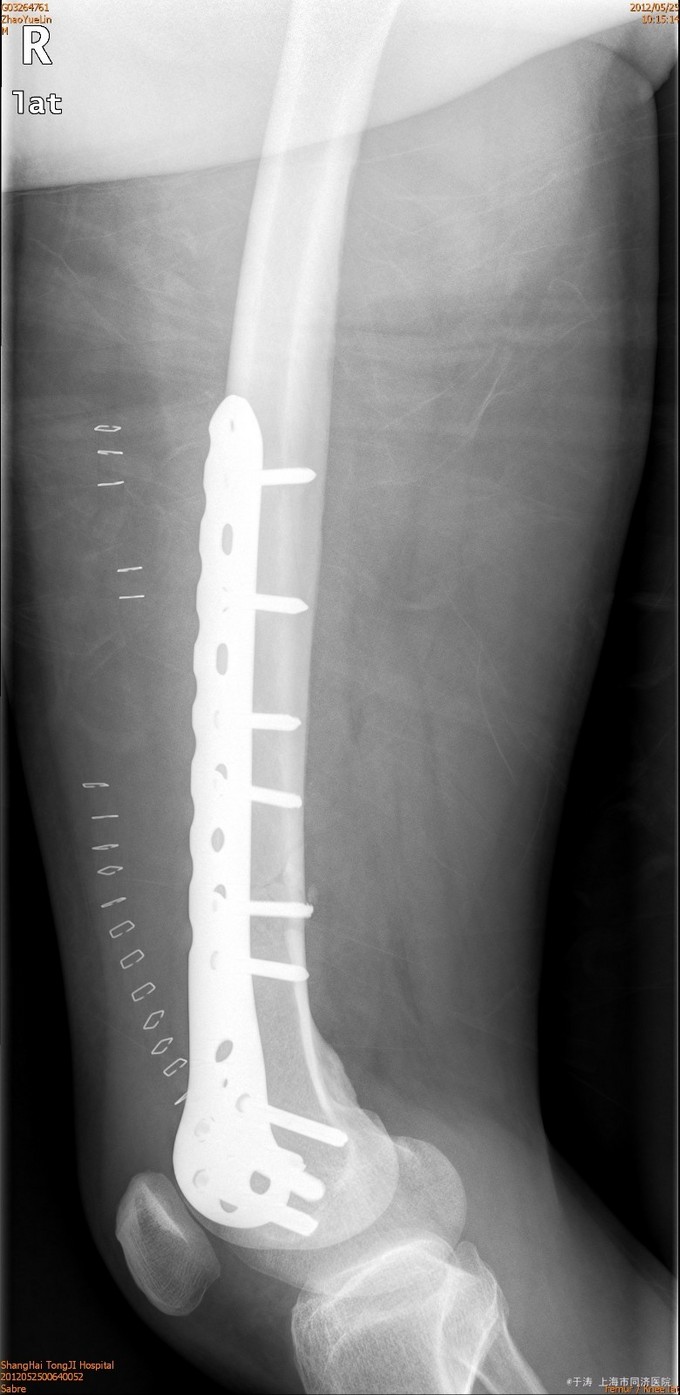

诊断为右股骨远端骨折,生命体征平稳后,行切开复位内固定术。

术后1年随访,功能良好,患者拒绝摄片和拔除内固定。对于股骨远端骨折,切开复位钢板内固定疗效可。